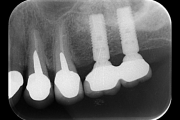

Ci consente di sostituire uno più denti mancanti inserendo nell’osso una o più viti di titanio che costituiscono delle radici artificiali sulle quali si possono creare protesi di diverso tipo.

Implantologia

Implantologia